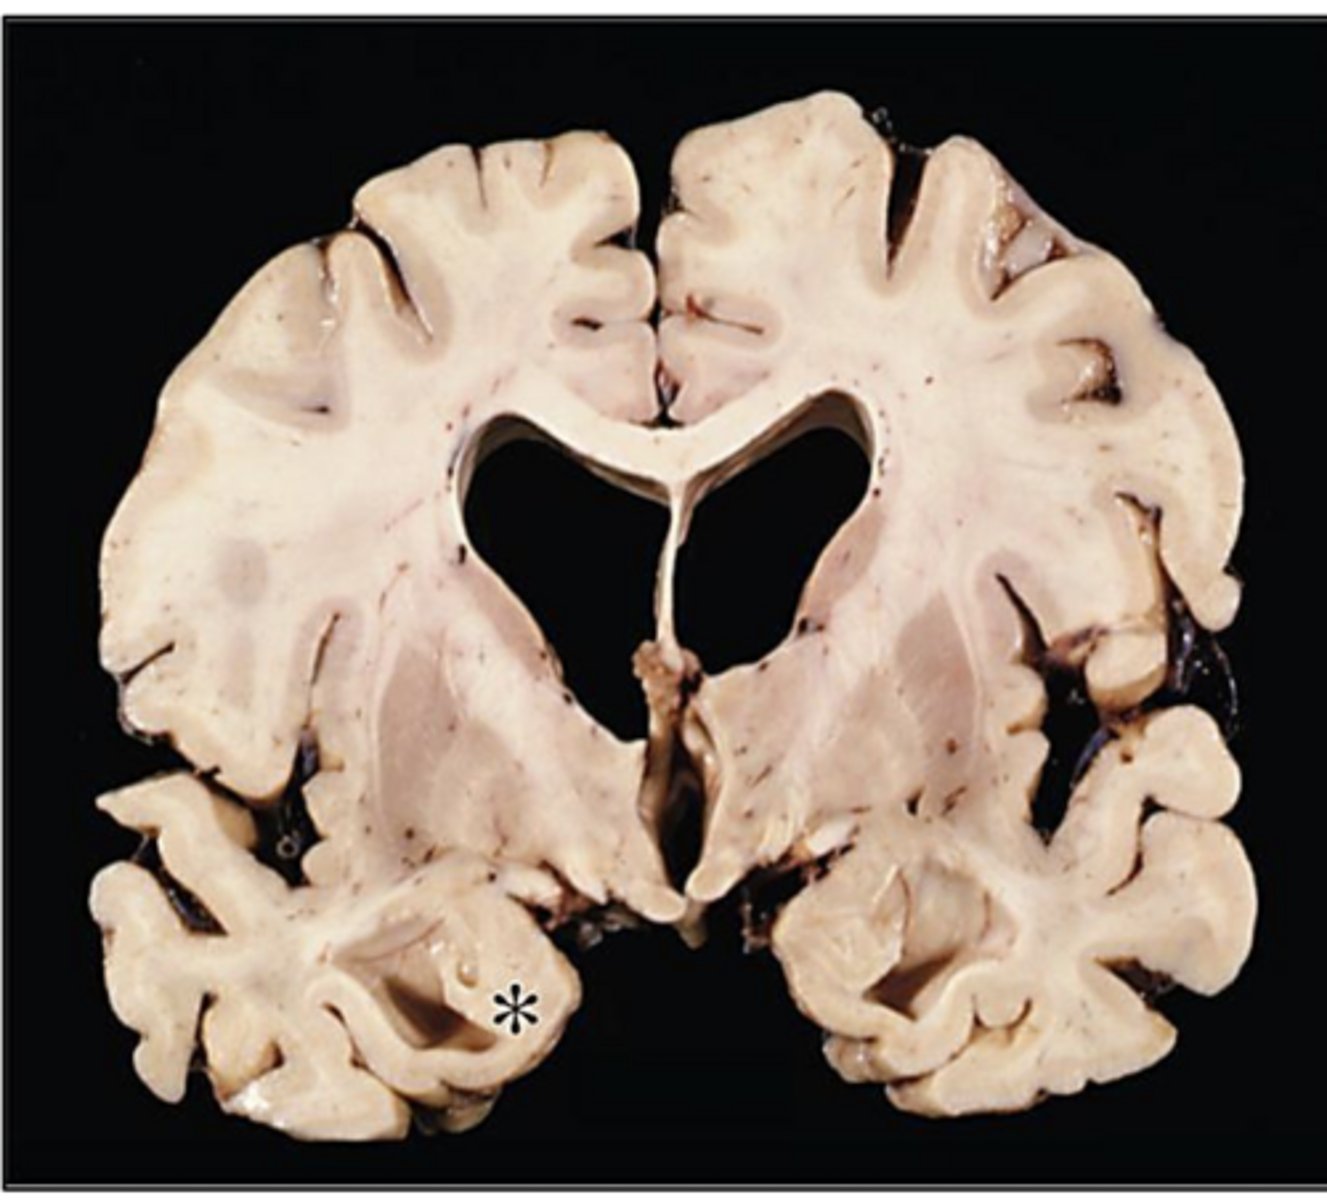

AD -> characteristic atrophy of the entorhinal cortex is seen, with resultant dilation of the temporal horn of the lateral ventricles

* = amygdala

small hippocampus in case of AD -> associated with memory loss